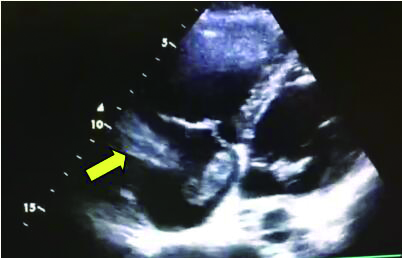

2 积极寻找补救性溶栓的治疗时机并非遥不可及例3 36岁,女性。主诉“活动后气短5 d、加重伴咯血1 d”。既往因月经不调,应用激素替代治疗20 d;否认手术、外伤及制动史。入院查体:神志清楚,体温36.8℃,血压110/75 mmHg,脉率118次/min,呼吸23次/min,脉氧饱和度90%(安静,空气氧),轻度乏氧征。双肺呼吸音清。心率118次/min,未闻及干、湿性啰音,心律齐,P2 > A2,心界无扩大,无杂音,腹软,无压痛,肠鸣音正常,双下肢无浮肿。神经系统查体未见异常。血气分析(空气氧)提示pH 7.415,PaCO2 38.3 mmHg,PaO2 89.90 mmHg,SaO2 89.90%;D-Dimer 1 684 ng/mL;FDP 8.670 μg/mL,FBG 3.510 g/L;PLT 151.0 G/L;cTnI 0.00 ng/mL,BNP 58.00 ng/mL;ALT 27 U/L,AST 17 U/L,CREA 53.7 μmol/L,血Na+、K+、Cl-大致正常;UCG提示:右室壁运动减低,左室壁运动不协调,各室壁厚度正常,三尖瓣环位移14 mm,右室面积变化率19%,各瓣膜形态及运动未见异常,收缩期三尖瓣房侧见少量反流信号,T1法估测SPAP:24 mmHg;双下肢静脉超声提示:右下肢深静脉血栓形成。心电图(图 8所示)提示窦性心动过速;CTPA提示双肺主干明确充盈缺损(图 9所示)。入院诊断:急性PE(中低危)。给予低分子肝素抗凝治疗。入院24 h内,大便时出现胸闷、心悸主诉,SpO2由93%(不吸氧)降至88%(储氧面罩吸氧,Flow 10 L/min);D-Dimer由入院时1 026 ng/mL升至4 100 ng/mL,血压110/70 mmHg。因血氧有恶化趋势遂决定给予静脉溶栓治疗(r-tPA 50 mg,2 h内泵入),溶栓治疗结束后2 h复查凝血提示D-Dimer 45 000 ng/mL。溶栓2 h患者症状明显好转;心电图提示窦性心动过速,SⅠQⅢTⅢ征象较前改善,胸前导联出现冠状T波(图 10所示)。溶栓后24 h复查CTPA右肺主干血栓明显消失,右心室较前明显缩小(图 11所示)。

| 图 9 入院时CTPA提示右肺动脉主干充盈缺损、左肺亚段水平充盈缺损、右心室增长 |

| 图 10 溶栓2 h心电图示窦性心动过速,SⅠQⅢTⅢ征象较前改善,胸前导联出现冠状T波 |

| 图 11 溶栓后CTPA提示原有血栓完全溶解、右心室较前明显缩小 |

患者特点及再灌注治疗时机选择:这是一例中高危PE患者接受抗凝治疗期间,大便后出现血氧改变但尚未出现血流动力学变化时,接受了补救性溶栓治疗并成功的案例。患者入院后出现的病情变化主要以缺氧程度加重为主,并没有血流动力学不稳定表现。提供补救性系统溶栓治疗出于两方面的考虑:①排便前后(床上)血氧出现很大的变化;②D-Dimer有升高趋势,警惕凝血和纤溶动态平衡的再次激活;③入院时CTPA血栓负荷较大,一旦血栓再次脱落可能会引发致命性的血栓事件发生。溶栓治疗后患者症状明显缓解、CTPA明显改善及溶栓2 h的心电图T波加深均提示溶栓治疗成功。